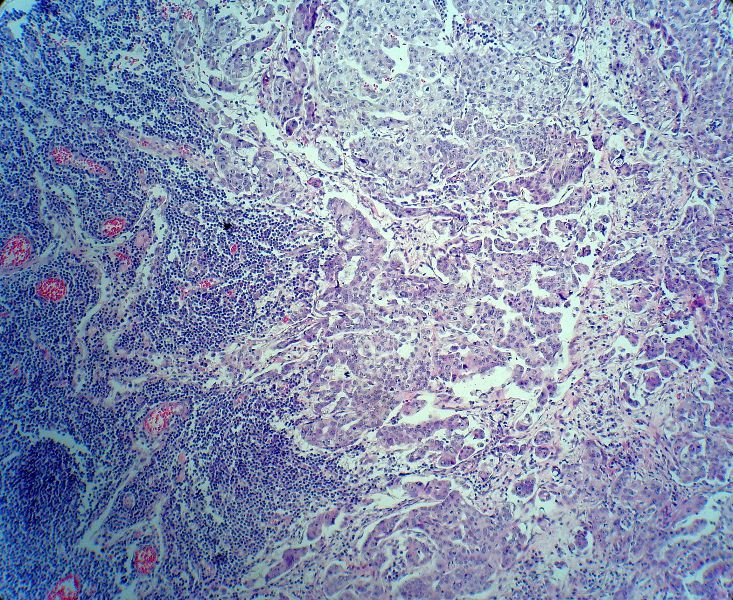

男,82岁,小肠穿孔紧急手术。

大体,小肠一段,长约60厘米,与粘膜面可见三个溃疡型肿物,肠系膜淋巴结肿大。

肿瘤呈巢片状分布,细胞大小相对一致,胞浆丰富,胞核呈细颗粒状,可见小核仁,血管较丰富,考虑神经内分泌肿瘤,加做免疫组化(Ki67、Syn、NSE、CgA、CD56)分级。

腺癌,部分为神经内分泌癌

神经内分泌癌。

肠系膜淋巴结